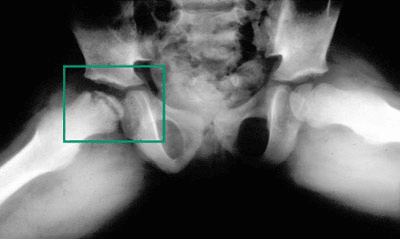

تشخیص این بیماری معمولا به توسط رادیوگرافی ساده داده می شود و در سیر بیماری معمولاً عکس برداری های متعددی برای مشخص شدن وضعیت پیشرفت بیماری از بیمار به عمل میاید.

در رادیوگرافی ساده در ابتدا تغییر در تراکم قسمتی یا همه اپی فیز سر استخوان ران دیده میشود و پس از چند ماه ممکن است تغییر شکل استخوان سر دیده شود. پزشک معالج با رادیوگرافی های سریالی که از لگن بیمار انجام می دهد وضعیت استخوان سر ران را تحت نظر می گیرد و برحسب شدت درگیری سر، نوع درمان بیمار را انتخاب می کند.

تشخیص بیماری پرتس معمولا به توسط رادیوگرافی ساده داده می شود